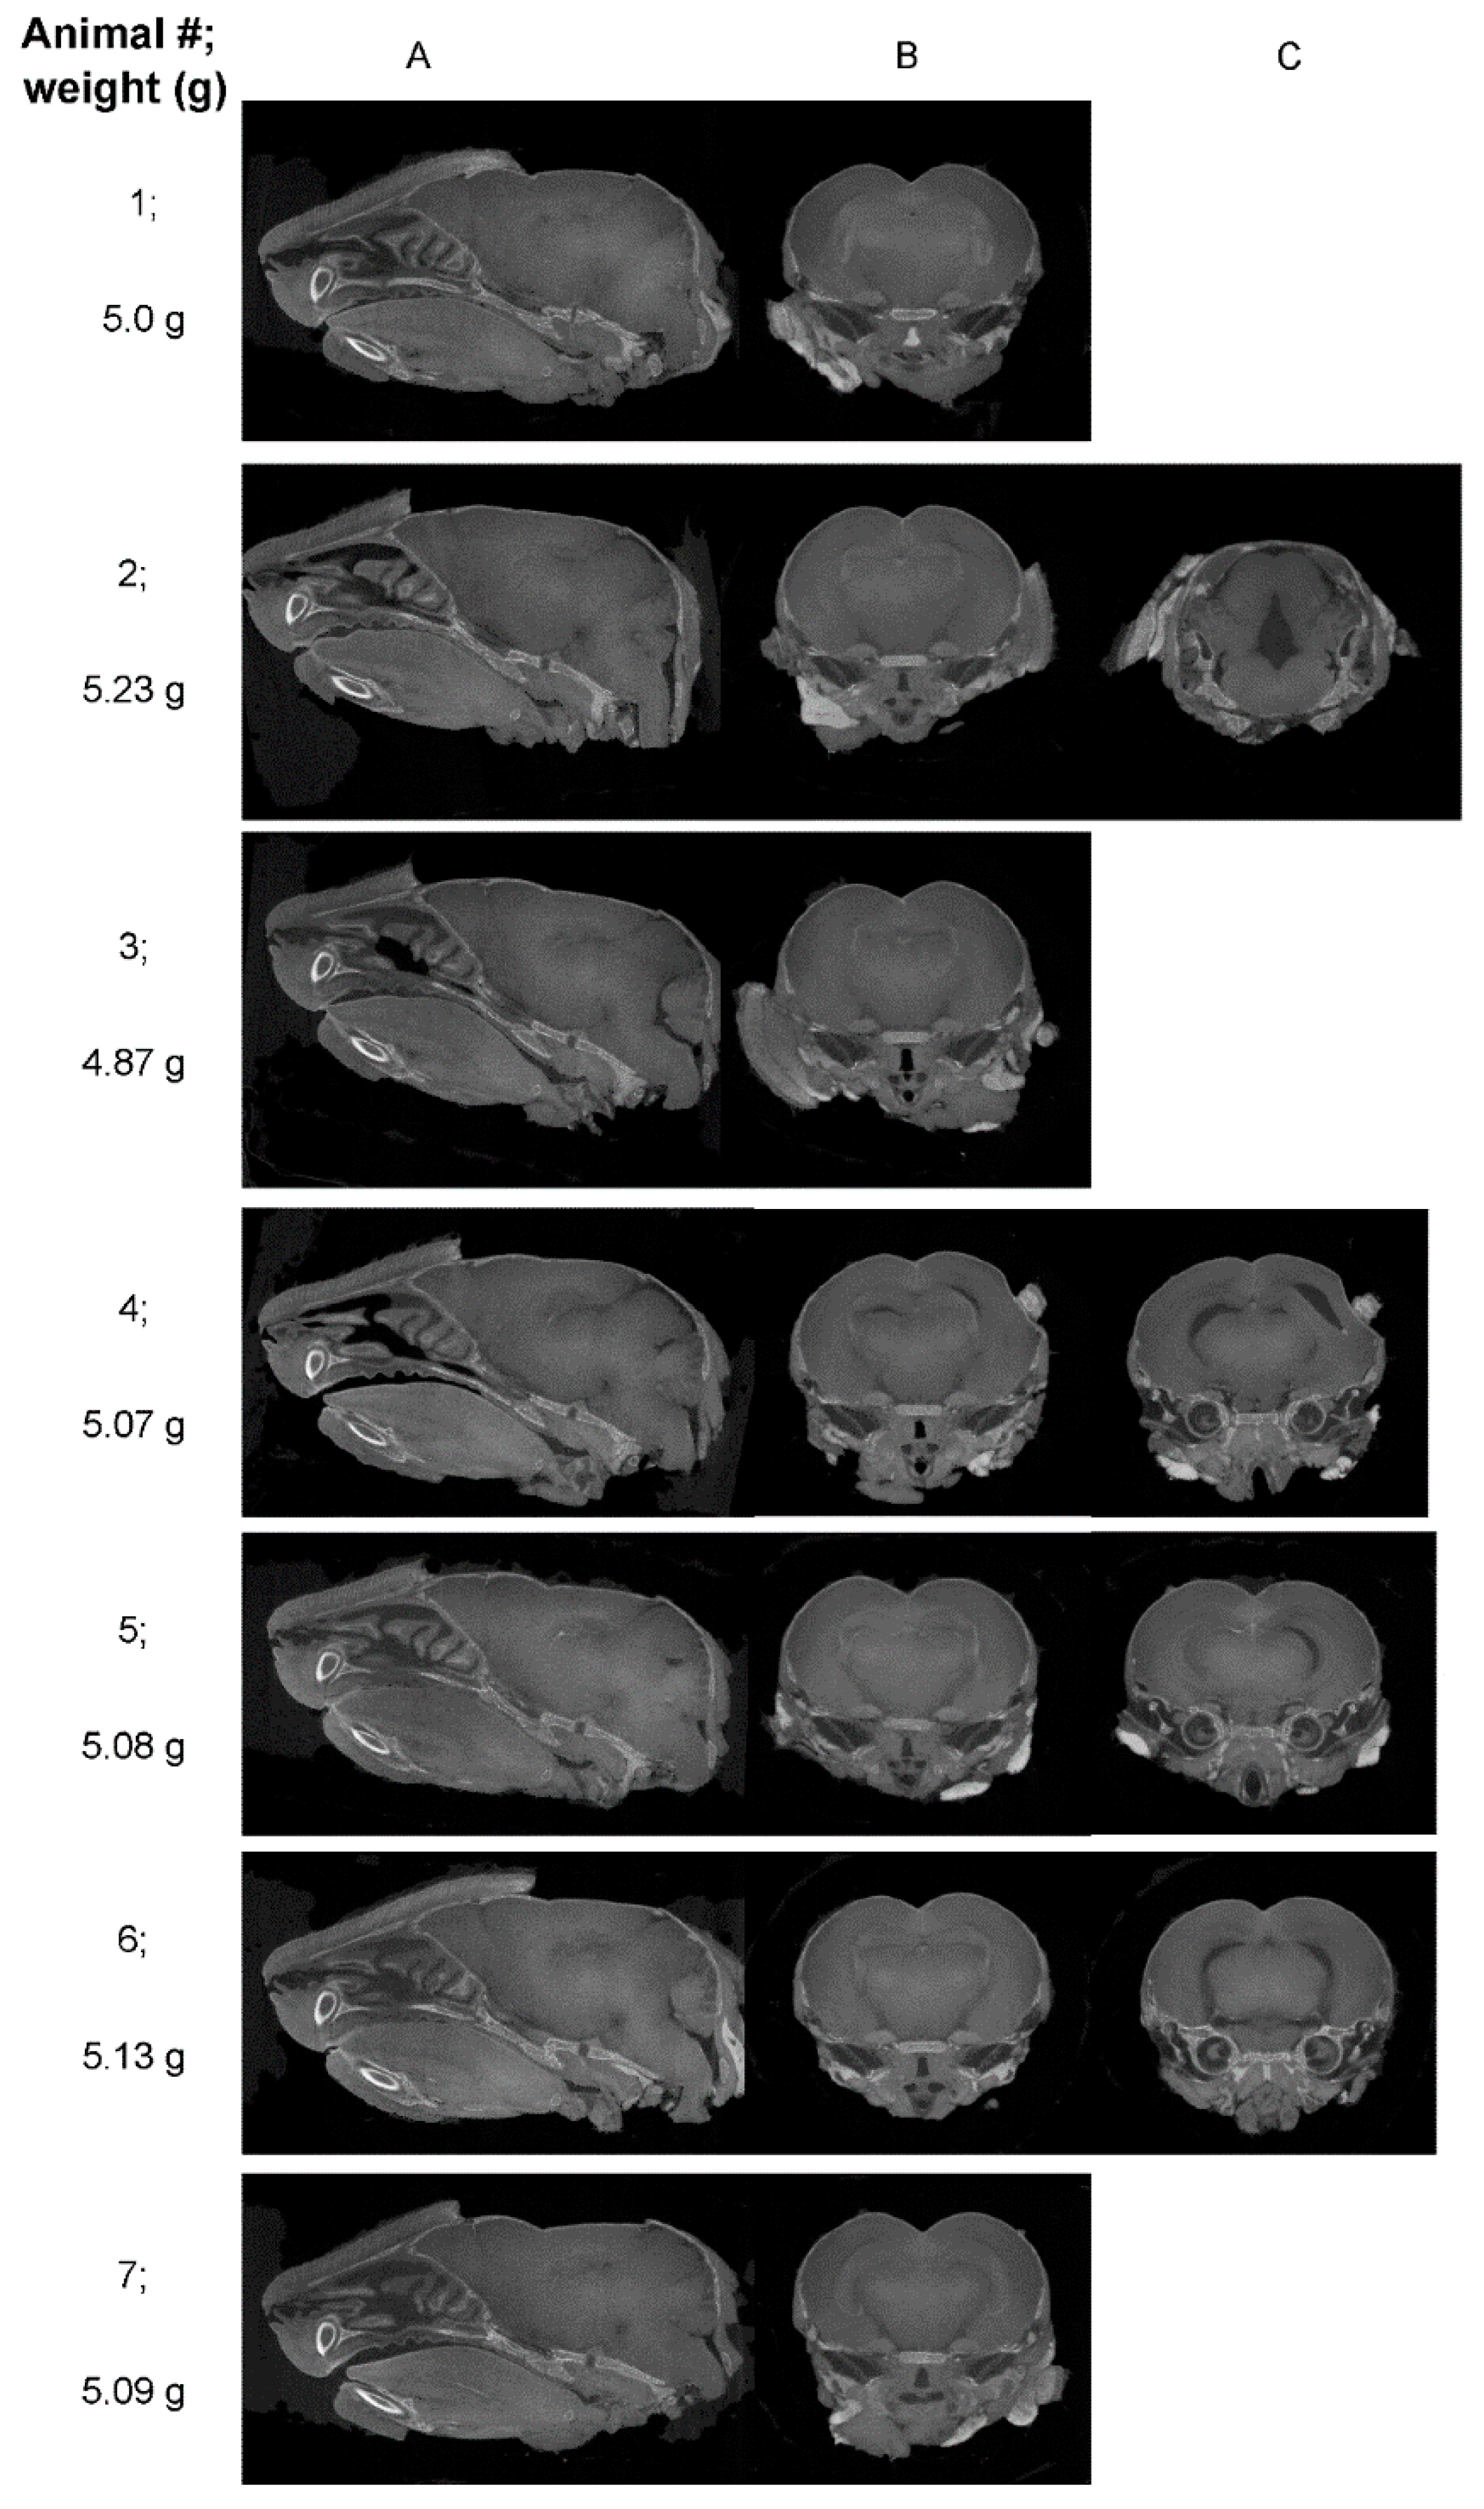

| Mouse ID | Weight (g) | Head length, L, width, W, depth, D (cm) | ZIKV RT-PCR | Movement |

|---|---|---|---|---|

| 1 | 6.40 | L=1.9; W=0.8; D=0.6 | positive | Mild hind limb dysfunction |

| 2 | 7.50 | L=2.3; W=1; D=1 | negative | normal |

| 3 | 6.64 | L=2.1; W=1.2; D=0.9 | positive | Mild hind limb dysfunction |

| 4 | 5.93 | L=2.1; W=0.9; D=0.7 | positive | Mild hind limb dysfunction |

| 5 | 7.37 | L=1.8; W=0.7; D=0.8 | negative | normal |

| 6 | 7.34 | L=2.1; W=0.9; D=0.7 | negative | normal |

| Mean ± SEM | Body Weight (g) | Head Length (cm) | Head Width (cm) | Head Depth (cm) |

| Mock (2, 5, 6) |

7.40 ± 0.05 | 2.17±0.07 | 1.03±0.09 | 0.87±0.09 |

| ZIKV (1, 3, 4) |

*6.32 ± 0.21 | 1.93±0.09 | 0.8±0.06 | 0.7±0.06 |

| p=0.007, t=5.042, df=4 | p=0.102, t=2.211, df=4 | p=0.091, t=2.214, df=4 | p=0.189, t=1.581, df=4 |

| Mouse ID | Reviewer 1 | Reviewer 2 | Reviewer 3 | Reviewer 4 |

| 1 | No pathological findings noted UI |

No pathological findings noted UI |

| 2 | Major gap at rear of brain ZIKV |

Asymmetrical gaps at the level of the hippocampus/thalamus ZIKV |

Asymmetrical, apparent volume loss in the hippocampus ZIKV |

Asymmetrical, increased space between hippocampal region and thalamus and towards the hind brain ZIKV |

| 3 | No pathological findings noted probably UI |

Some gaps, but no asymmetrical volume loss UI |

Slight gaps between hippocampal region and thalamus probably UI |

| 4 | Multiple asymmetrical gaps, penetrating across midbrain ZIKV |

Clear asymmetrical gaps between structures, with majority of abnormalities around thalamus and hippocampus, continuing through the posterior brain ZIKV |

Very clear asymmetrical abnormalities, particularly at level of posterior hippocampus, and continuing more posteriorly ZIKV |

Gaps between hippocampus and cortex (right) and thalamus (left); Gap (right) appears to go through majority of the brain ZIKV |

| 5 | Maybe minor anomalies; UD |

Asymmetrical gaps between hippocampus and thalamus ZIKV |

Abnormality in region anterior to nuc accumbens and at level of striatum (less defined); Clear asymmetry at the level of the poster hippocampus; ZIKV |

Gap in between hippocampal region and thalamus probably ZIKV |

| 6 | Symmetrical gaps, penetrating across images through midbrain ZIKV |

Clear gaps at hippocampus, continuing throughout posterior brain ZIKV |

Very clear abnormalities, particularly at level of posterior hippocampus and extending posteriorly ZIKV |

Gap in between hippocampal region and thalamus on left and right side, which runs through majority of brain ZIKV |

| 7 | Maybe minor anomalies UD |

Minor abnormalities UI |

Some minor abnormality, which may be an imaging artifact or normal anatomical variation UD |

Slight gap between hippocampal region and thalamus; probably UI |